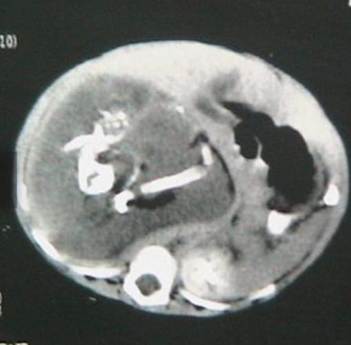

Her parents complained about a gradually increasing hard lump in her upper abdomen since last 6 months which was extending upto pelvis with occasional pain. There was no maternal illness, exposure to radiation or drug intake during pregnency. There was no family history of multiple pregnencies. There was no other gastrointestinal or genitourinary symptom. At Clinical examination a, bulky, firm, rounded mass of 14cm×16cm was palpated in Rt hypochondriac, epigastrium & umbilical region. The plain abdominal radiograph revealed a right upper quadrant mass containing calcified densities identifiable as fetal parts. CT Scan of abdoman with oral and intravenous contrast reveals a large retroperitoneal soft tissue mass with cystic component which is separated from Rt. Kidney. Her haemoglobin level was optimum and other haematological parameters were within normal limit.

Laparotomy was performed through a supraumbilical transverse incision. At surgery, a thick walled solido cystic mass was found in the retroperitoneal region which compressed IVC and duodenum and small gut were displaced towards left side. The mass enveloped entirely by a saclike capsule withan umbilical cord. The cord connected the mass to the branch of abdominal aorta.

In this case, during surgery, the fetus was found to be surrounded by a capsule that grossly ressmbled a fetal membrane. It contained a variable amount of fluid and was connected by a peduncle to a vascular structure of the host twin. Preoperative diagnosis is possible by radiograph, ultrasonography and computer tomograph. Though a rare anomaly, fetus in fetu can be identified radiologically in the pre-operative period.10 Radiological differential diagnosis included teratoma and meconium pseudocyst. 11 Pathological controversy arises during differentiation of fetus in fetu from a mature or well organized teratoma. According to willis,12 the presence of axial skeleton with vertebral axis and an appropriate arrangement of other limbs and organ goes more in favour of fetus in feta. Consistent with the theory of Willis, in my case, the vertebral column was detected by the radiologist. It was radio opaque as it was relatively calcified. However review of literature showed that in about 9% of case of fetus in fetu, no vertebral column was found even on radiological examination. 13